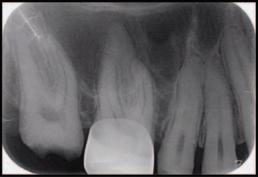

FIGURE 2: Left: Periapical radiograph pre endodontic treatment. Right: Post-endodontic treatment radiograph showing the presence of root canal filling material (AH Plus) inside the inferior alveolar canal.

Radiographic examinations consisted of digital orthopantomogram (OPG), peri-apical (PA), and cone beam computed tomography (CBCT) scans. The scans revealed that the lower left first molar root canals were obturated with a radiopaque material, and showed root canal filling extending beyond the apices of the tooth and approximately 5cm along the mandibular canal ( Figures 1 , 2 and 3 ).